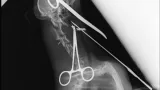

Maleni pas mješanac pogođen je dijabolom u vrat, a budući da je metak ostao smješten na nezgodnom mjestu blizu kralježnice, veterinar Mate Karaula iz Daruvara koji liječi Lenu, odustao je od vađenja metka zbog daljnjeg rizika po kujicu.

Prema nalazu veterinara dr. Mate Karaule, rendgenska snimka pokazala je da se metak, točnije dijabola, nalazi u području između atlasa i aksisa – dijela vratne kralježnice.

- Veličina projektila procijenjena je na 6,10 do 5,16 milimetara, a zbog dubine položaja i blizine kralježnice procijenjeno je da bi pokušaj vađenja mogao izazvati ozbiljne komplikacije. Zbog toga se odustalo od kirurškog vađenja metka.

Pas je primio injekcijsku sedaciju, obavljene su dvije rendgenske snimke i kirurška obrada rane, kazao nam je dr. Karaula.